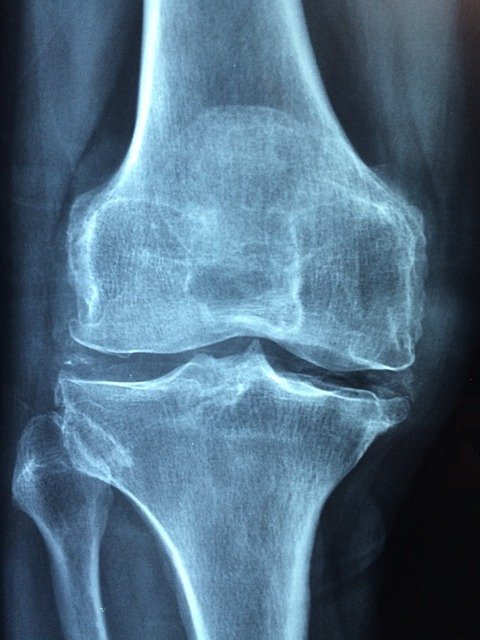

중년 이후 여성은 폐경으로 인한 호르몬의 변화로 인해 복부지방의 증가와 동시에 근육량이 감소한다. 중년 이후에 비만ㆍ근감소증이 있으면 인슐린 저항성이 높아지고, 당뇨병 발생 위험도 커진다. 관절염은 근육의 양적ㆍ질적 저하의 원인인 질환으로, 근감소증과 관련이 있다.